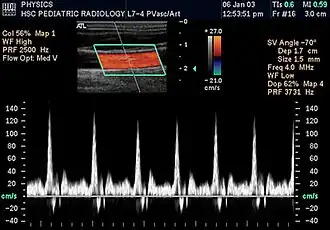

In the 1970s, Strandness and the bio-engineering group at the University of Washington, turned their attention to the use of real-time B-mode scanning. This type of ultrasound would enable physicians to see the vascular structures in real-time. Further research allowed B-mode imaging to be combined with Doppler ultrasound, providing real-time views of the vascular structures and simultaneous hemodynamic information. Today, this type of duplex scanning is used in a variety of ultrasound specialties.[6]